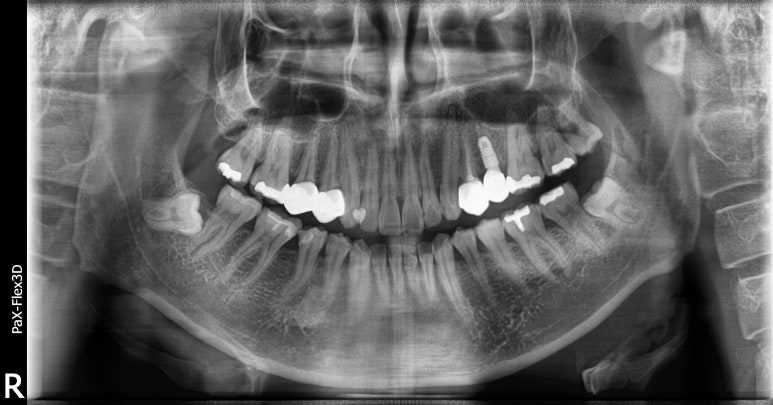

다행히 환자분은 수술이 잘 마무리되었고, 보철물까지 무사히 부착이 완료되었습니다.

2022-11-30

만약 환자분께서 중간에 스케줄로 인해 출국하지 않으셨다면 완료 시점을 한 달 정도 앞당겨

총 3개월만에 모두 완료할 수 있었지만 아쉽게도 출장으로 인해 한 달 정도 딜레이가 되었네요.